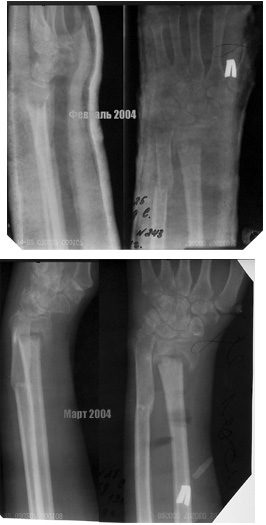

Травма в конце ноября 2003. Лечение - гипсовая лонгета по настоящее время. На контрольных рентгенограммах видно отсутствие консолидации, рассасывание в области перелома лучевой кости, остеопоротические изменения костей. Есть также гипэстезия 4,5 пальцев кисти, выраженная атрофия мышц. Функция кисти=0.Думали, что можно сделать: однозначно нужно выполнять освежение отломков, костную пластику, остеосинтез. Причем не медлить! Вопрос в том, как зафиксировать, все упирается в опасения прорезывания любых фиксаторов. Кроме того - что делать с локтевой костью - она работает как распорка. Резецировать ли ее головку, или имеет смысл сегментарно резецировать диафиз с последующим остеосинтезом?Просьба поделиться своими соображениями.

Не совсем согласен с вашим решением * не медлить* с фиксацией перелома лучевой кисти при отсутствии функции кисти. После столь продолжительной и,

как видно по рентгенограммам, бесполезной иммобилизации и мышечная атрофия, и порозность фрагментов очевидно являются следствием отсутствия функции. На данном этапе я бы скорее отправил больного к физиотерапевту на разработку движений пястно-фаланговых и межфаланговых суставов, если недеель через 6 тугоподвижность суставов начнет разрешаться и появится надежда на восстановление функции кисти, тогда и можно рассматривать различные подходы (удлинение луча или костная пластика с фиксацией Т-образной пластиной или укорачивающая остеотомия локтевой кости и т.д). Если после курса физио никаких намеков на функциональность кисти не появится при сохранении жалоб на боли вокруг лучезапястного сустава, то, пожалуй, можно будет ограничиться артродезом с одновременной пластикой несращения (так или иначе, пластина укладывается по тыльной поверхности, так, что обнажить зону нестращения и восстановить длину луча не должно быть большой проблемой)

Вероятней всего, у больной развилась рефлекторная симпатическая дистрофия (нейротрофическая дистрофия или синдром Зудека), о чем косвенно "говорит" пятнистый остеопороз кисти и функция кисти 0. Вероятно еще, у больной, длительный отек кисти, пятнистая синюшность.

Если больную лечить оперативно, функцию кисти можно потерять навсегда.

Считаю больной необходимо консервативное лечение 6 месяцев.

Затем решать вопрос об оперативном лечении.

Ложного сустава дистального эпифиза или метаэпифиза лучевой кости еще никогда не видел (допускаю, что мало видел).